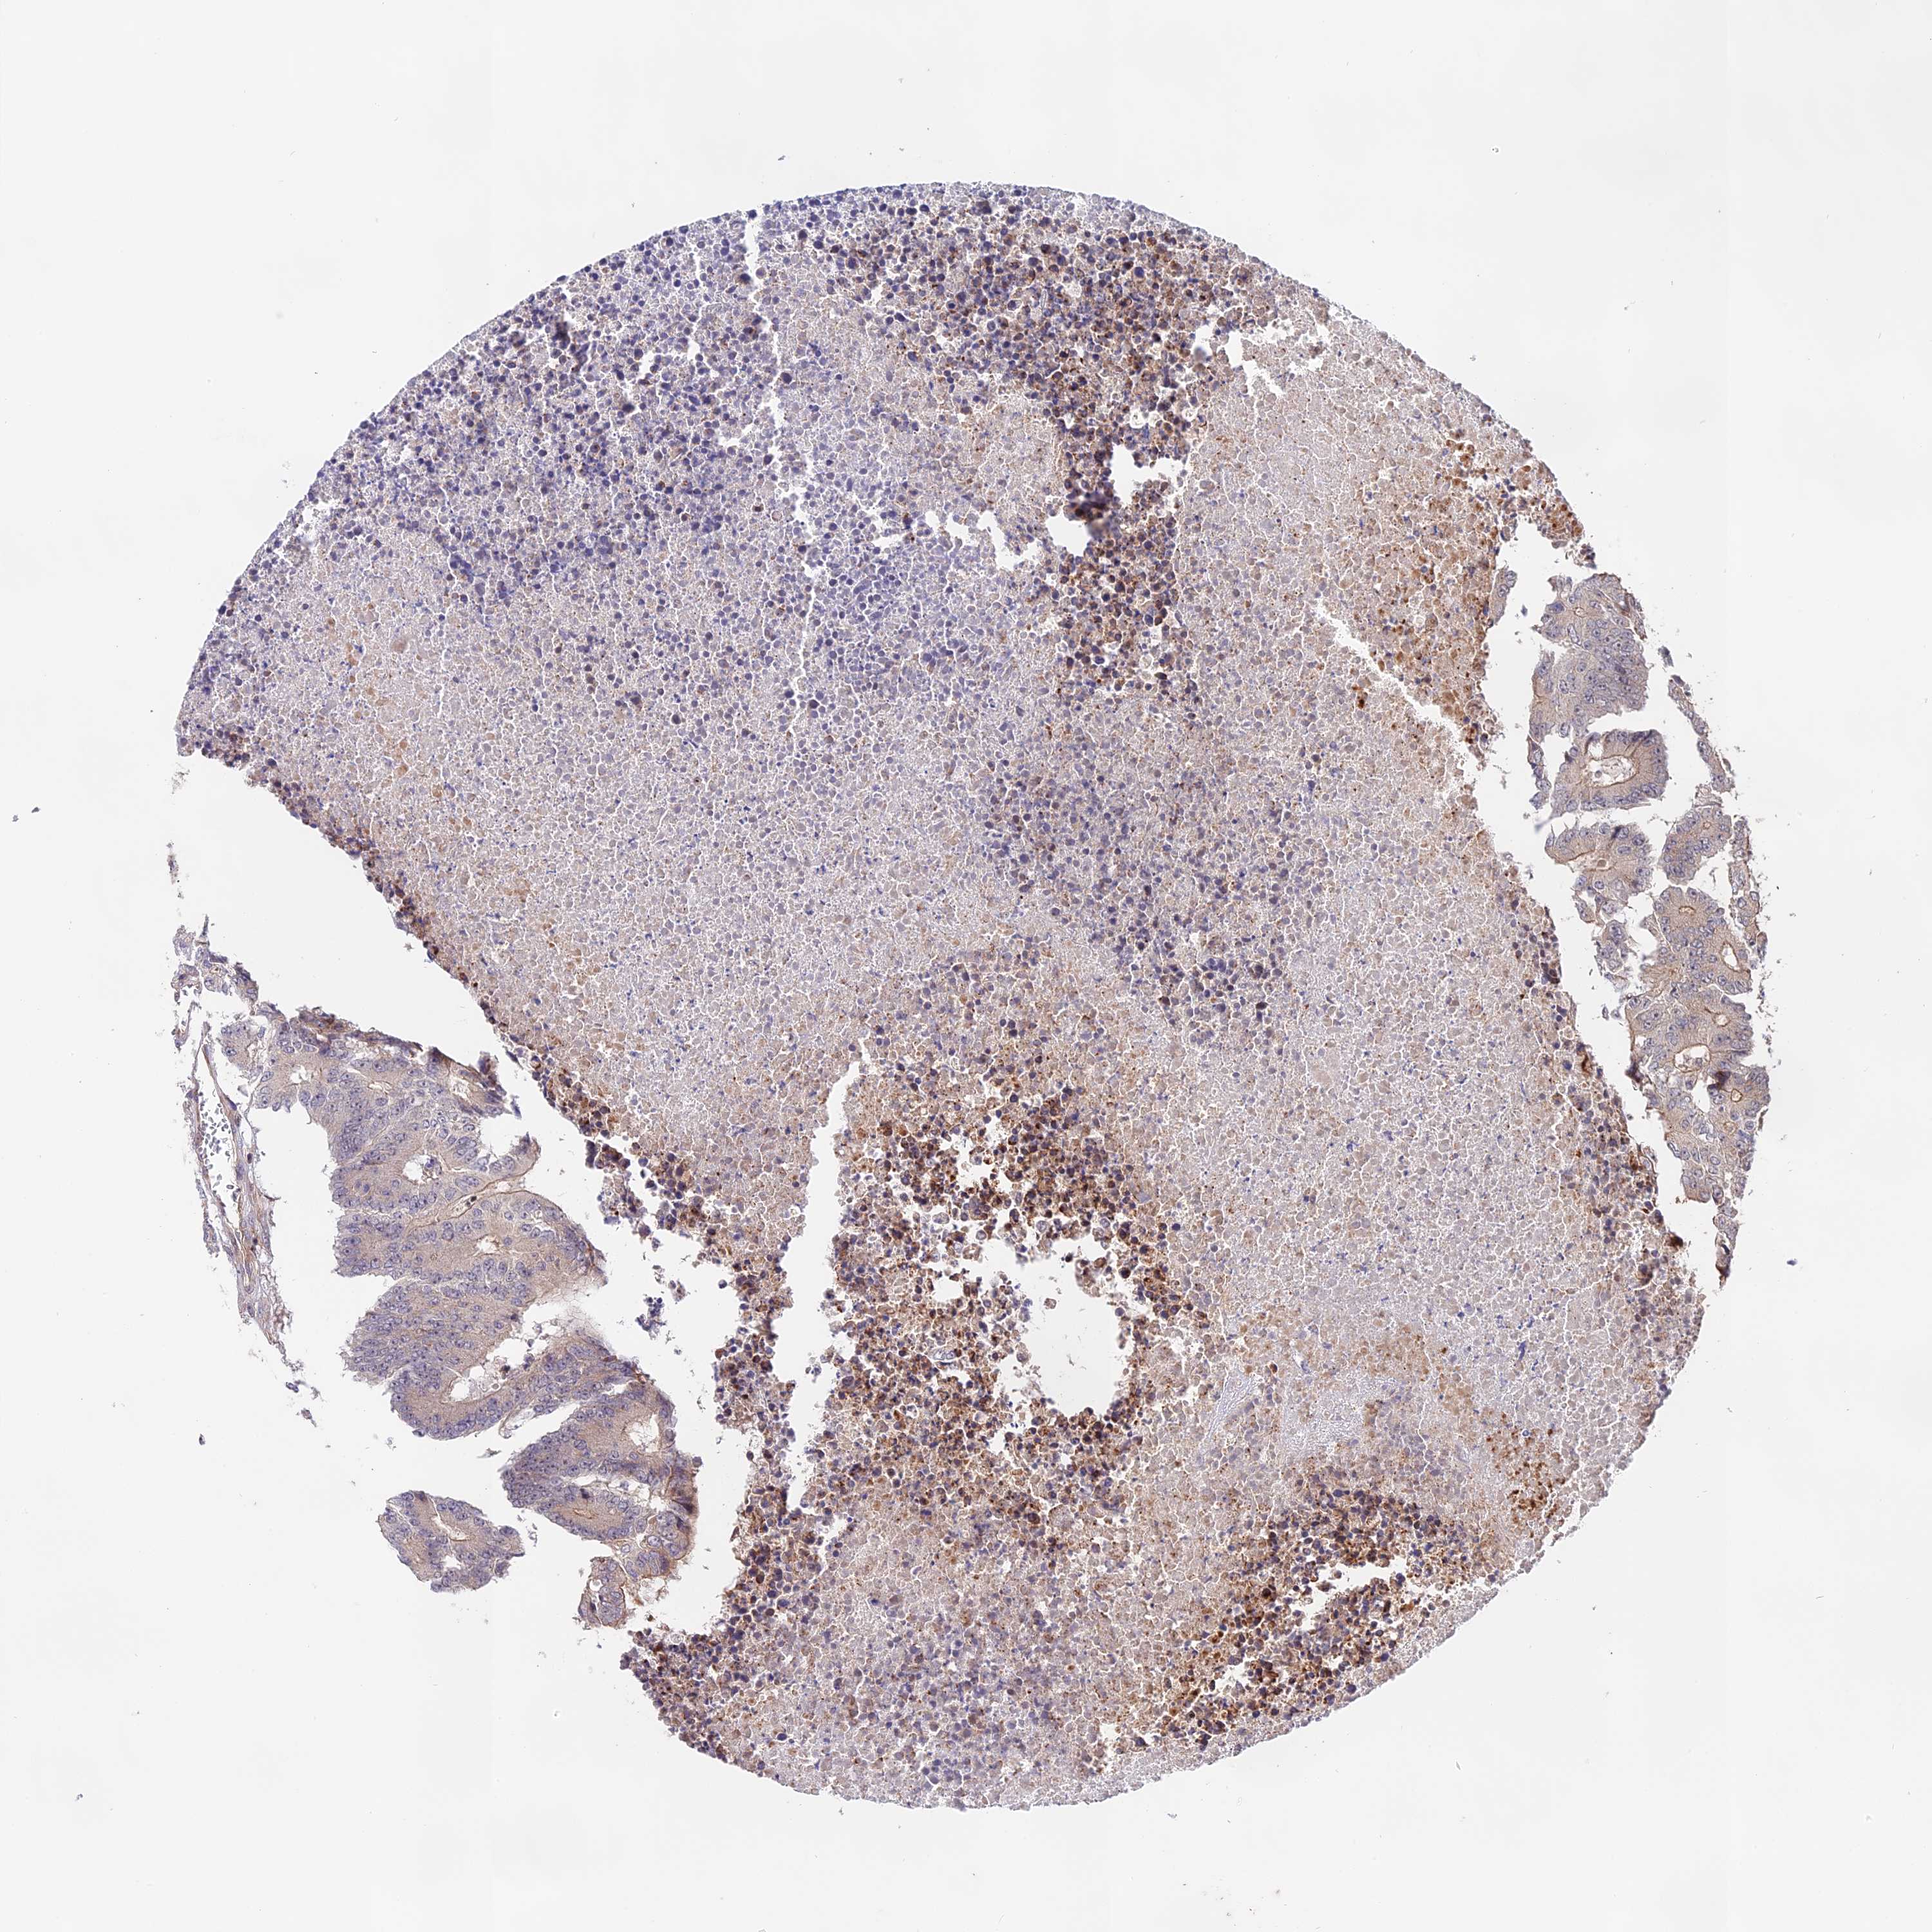

CANCER COLORECTAL CANCER Show tissue menu

Colorectal cancer

Human cancer

Colon adenocarcinoma